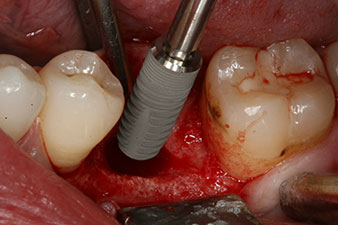

No obstante, seis semanas después de la extracción, tras la disección del colgajo mucoperióstico, se observó una osificación incompleta en el área del antiguo alvéolo mesial.

Tras la extirpación minuciosa del tejido de granulación, se incorporó el implante tal como se había planificado (blueSky, bredent).

El torque en el momento de la carga mecánica fue de 43 Ncm. Asimismo, después de atornillar un poste de medición especial adaptado al sistema de implante (SmartPeg), el valor ISQ se determinó con la sonda del módulo Osstell ISQ de W&H.